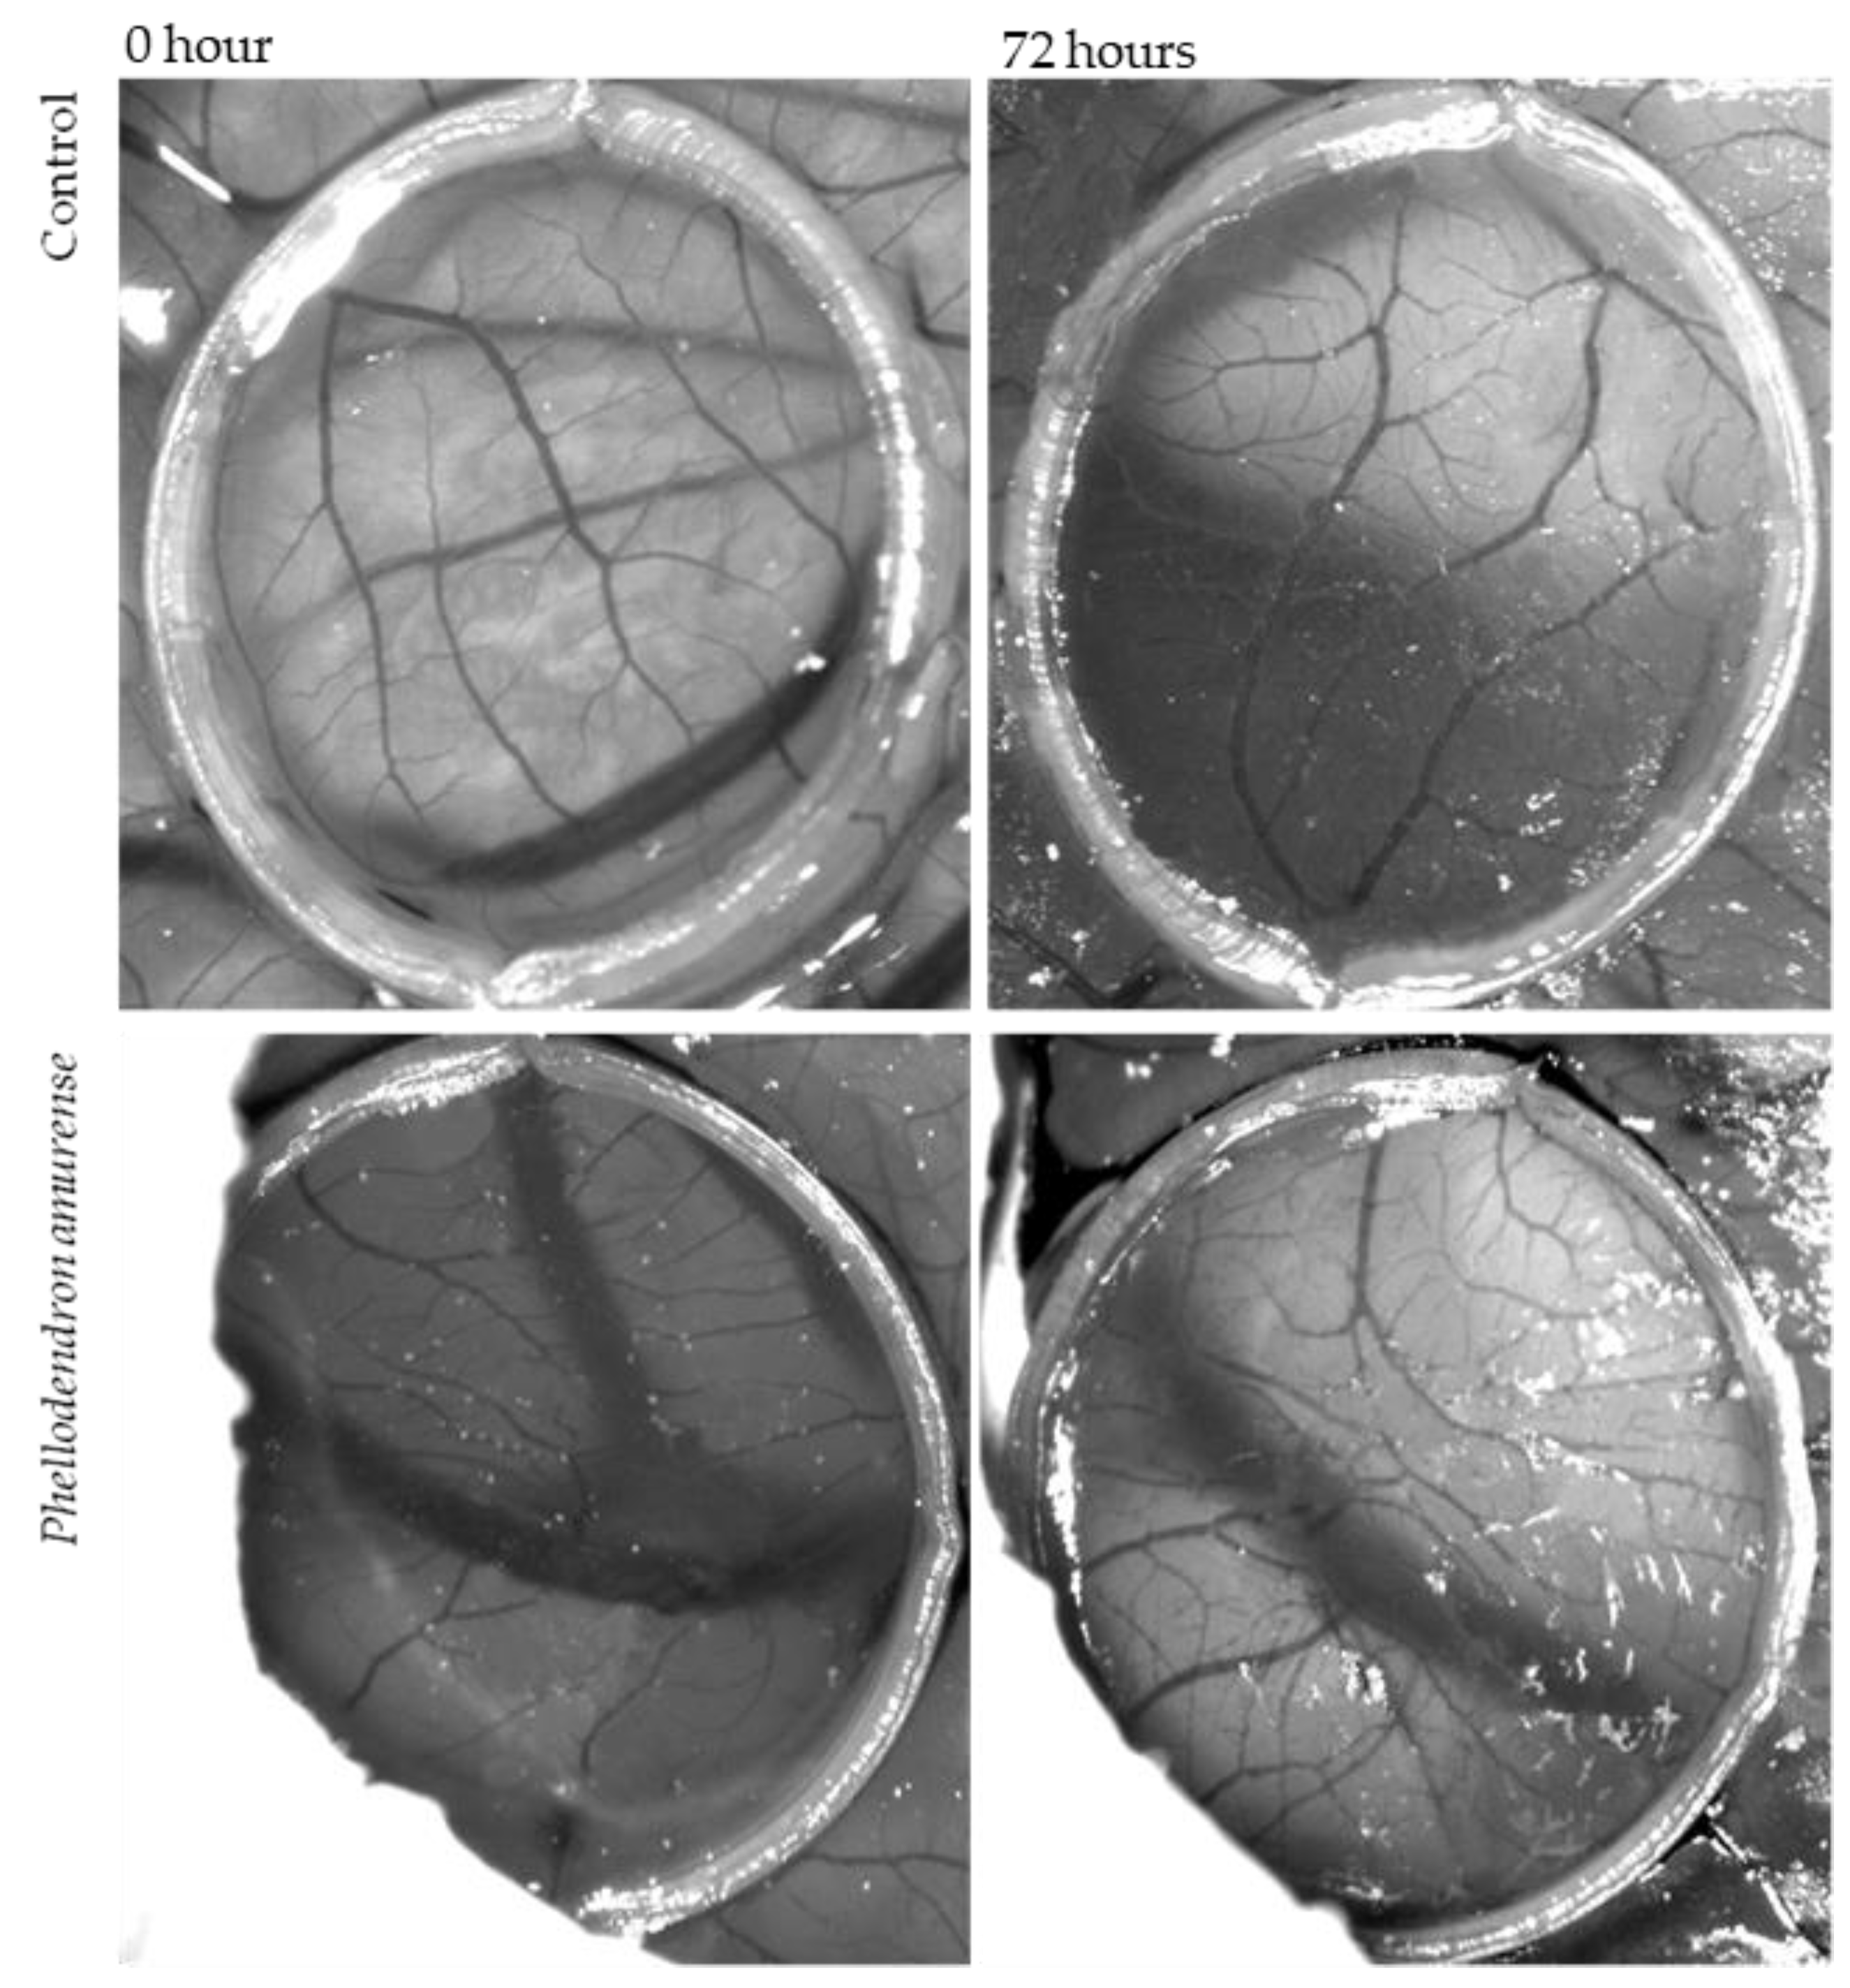

3.6. Antiangiogenic Activity

The CAM assay was used to examine whether Phellodendron amurense has any effect on neovascularization in ovo. The inhibition of angiogenesis was analysed by two methods, which gave us information about total branching points and total vascular zone, which means the vessels’ density.

The anti-angiogenic effect of dry PA residues from tincture dissolved in saline solution (1 mg/mL) on the treated CAM is shown in Figure 8. It was microscopically observed that tested solutions of PA inhibited angiogenesis in the CAM, causing the reduction in the vascular density compared to the control (saline solution) (Figure 9). The results can also be interpreted in the percentage of vessels density. Whereas in the case of control 27.5% of the figure can be considered vessels, this value is only 10.9% for the CAM treated with tested solutions of PA bark.

Figure 8.

Photographs of HET-CAM without sample at the beginning of the experiment and after 72 h. HET-CAM treated by Phellodendron amurense Rupr. bark solution at the beginning of experiment and after 72 h.

The second method for measuring the antiangiogenic potential of the tested PA solution was based on the enumeration of bifurcation points. An increase in the number of vessels crossing the delimited area was observed in the control (saline solution) (2.4 ± 0.1) and in CAM exposed to PA (1.7 ± 0.4). The present result demonstrated that Phellodendron amurense Rupr. exhibited a significant decrease in the branching of new capillaries from the existing basal vessels compared to the control after 72 h of treatment.

The present study showed the anti-angiogenic activity tested in ovo of Phellodendron amurense Rupr. for the first time. Both methods of measuring anti-angiogenic effects were compared and showed very similar results. In both cases (vascular zone and vessel sprouting), a reduction in angiogenesis was found. Phellodendron amurense Rupr. was able to significantly induce blood vessel response to stimuli. These results suggested that PA could be particularly attractive for the treatment of cancer according to its antiangiogenic properties. Moreover, the extract of Phellodendron amurense Rupr. did not affect the embryo viability.